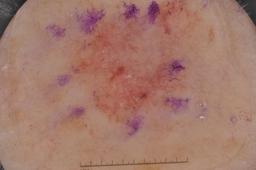

{

"age_approx": 80,

"anatom_site_general": "lower extremity",

"concomitant_biopsy": true,

"dermoscopic_type": "contact non-polarized",

"diagnosis_1": "Malignant",

"diagnosis_2": "Malignant melanocytic proliferations (Melanoma)",

"diagnosis_3": "Melanoma Invasive",

"diagnosis_confirm_type": "histopathology",

"image_type": "dermoscopic",

"lesion_id": "IL_0701451",

"melanocytic": true,

"sex": "male"

}